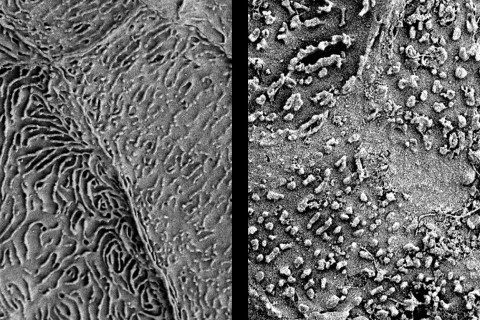

Pyyhkäisyelektronimikroskooppikuvassa suun limakalvon pintasoluja: vasemmalla terve limakalvo, oikealla sädetetty limakalvo.

– Syöpähoidot aiheuttavat ”kriisin” suuontelossa ja niiden välitön vaikutus näkyy pahimmillaan suun haavaisena limakalvotulehduksena eli mukosiittina. Tutkimuksessamme havaittiin sädehoidon seurauksena vielä usean vuoden jälkeenkin suun limakalvon heikkeneminen, kuten soluvälitilojen laajeneminen ja pintasolujen mikrorakenteen hajoaminen. Saadun paikallisen sädeannoksen suuruus ei vaikuttanut merkittävästi muutoksiin, vaan niitä esiintyi myös pienemmän sädeannoksen saaneilla limakalvoalueilla, Kullaa kertoo.

Kullaan mukaan merkittävä havainto on sädehoidon aiheuttama suun limakalvojen pintasolujen mikrorakenteen vaurioituminen, joka estää syljen ainesosien kiinnittymisen limakalvon pintaan. Tämä aiheuttaa kuivan suun tunnetta normaalista syljen erityksestä huolimatta. – Jatkoimme tämän tuloksen pohjalta tutkimuksia suun limakalvon pinnan ja syljen vuorovaikutuksesta.